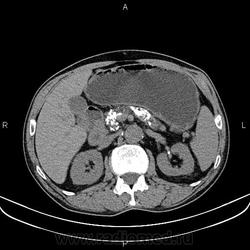

Каменюки в поджелудочной железе?

Добавил КТ. Жаль криволинейной реконструкции на станции нет.

Недавно был такой случай, долго думал и искал... Потом на радиопедии нешел что это хронический панкреатит, да и по поводу обзорки, на обзорной рентгенограмме не стоит все похожие кальцинаты списывать на поджелудочную так как это может быть и аденокарцинома толстой кишки.